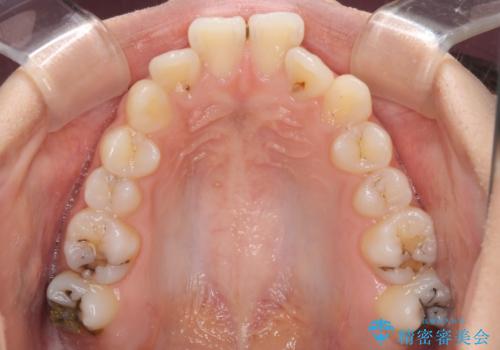

下顎前方位の骨格のため、下顎歯列に対して上顎歯列の幅が狭くなっていました。

急速拡大装置を用いて上顎骨を側方に拡大し、上顎の叢生を解消するとともに下顎歯列拡大により下顎の叢生も解消することとしました。